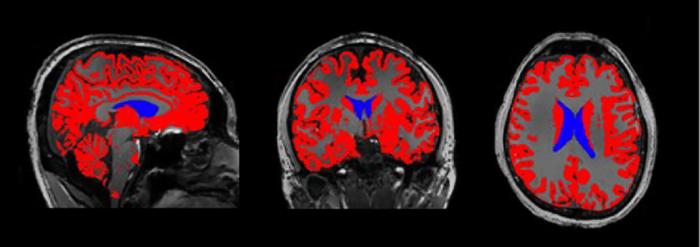

MRI image of the brain with the lateral ventricles colored in blue. The ventricles are filled with cerebrospinal fluid.

The exact meaning of the fMRI signal coming from the brain—specifically the lateral ventricles—remains a mystery for future studies. fMRI signals depend on the magnetic properties of hemoglobin in the blood, but there is none in cerebrospinal fluid. The signal could be related to a combination of processes associated with brain activity and waste removal.